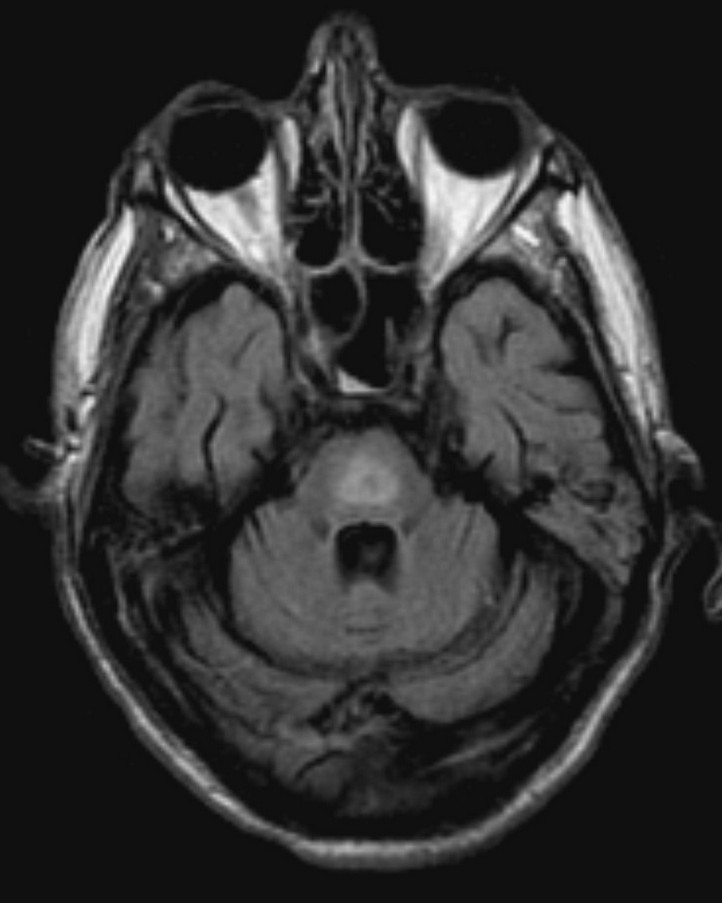

另一方面,大腦充滿了高度分化的精細細胞,無法承受快速的膨脹或縮小,比起一般細胞更容易受傷。寡突細胞(Oligodendrocyte)負責製造神經細胞的外牆——「髓鞘」,如果他受傷了,神經細胞一旦失去了髓鞘,就不能正常運作了!於是乎,腦細胞縮水造成了大腦當機,病人的意識就出現變化了!這就是——「滲透壓去髓鞘症候群」(Osmotic demyelination syndrome)。

當一天血清鈉離子濃度上升超過 8 mmol/L 的時候,就有可能會產生「滲透壓去髓鞘症候群」,病人會發生意識不清、無法說話、吞嚥困難等等症狀,甚至還會產生癲癇!神奇的是,這些症狀經常會延遲兩天左右才發生,這時往往血液鈉離子濃度檢驗起來已經「挺正常的」,當醫生和病人認為低血鈉已經被矯正回來的時候,可能惡夢才正要開始!